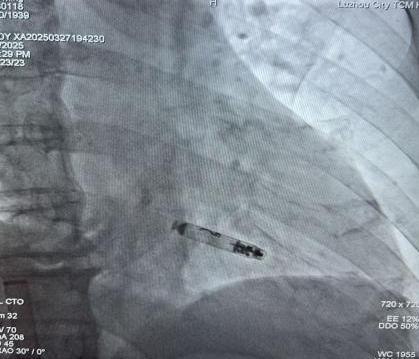

起搏器釋放后影像

劉大爺?shù)氖中g(shù)在朱彬帶領(lǐng)下實(shí)施,在局麻下進(jìn)行。通過股靜脈將約二分之一7號(hào)電池大小的無(wú)導(dǎo)線起搏器送入他的右心室,再利用獨(dú)有的螺旋錨定裝置牢牢地將其固定于心肌。術(shù)中、術(shù)后參數(shù)測(cè)試均良好,如今患者術(shù)后恢復(fù)良好,心臟逐漸恢復(fù)“活力”,未再出現(xiàn)過頭暈癥狀,術(shù)后隨訪提示預(yù)估壽命20-30年。